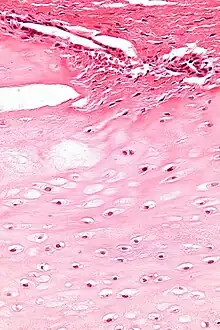

| Micrograph of an enchondroma. H&E stain. |